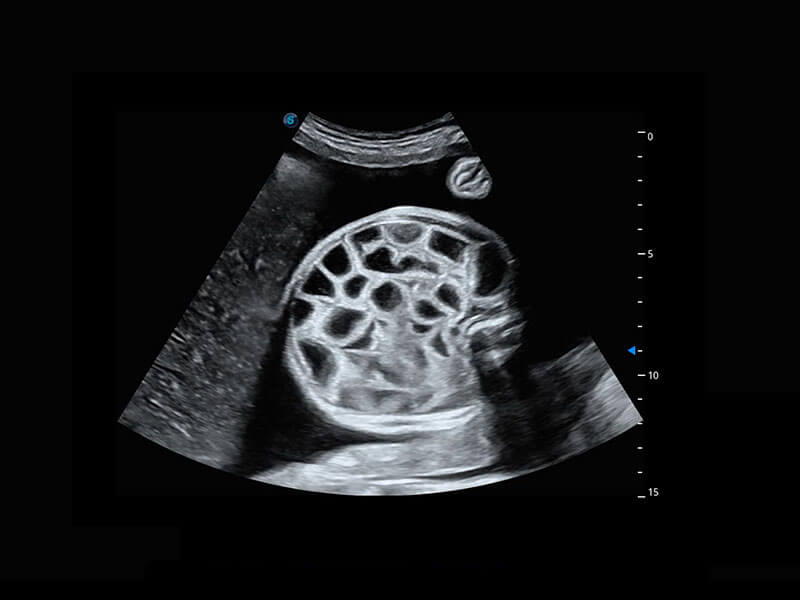

腔内三维-宫内节育器

P60提供简单易学易用的高端诊断工具,为您中晚孕筛查提供快速清晰的解剖信息。

1 OFD(HC): 87.03 mm

HC: 251.00 mm

GA: 27w 1d

HC/AC: 96.13 %

2 BPD: 70.56 mm

GA: 28 w 2d

S-Fetus(acq.)

&

S-Fetus(meas.)

S-Fetus能够助您在实时扫查过程中自动识别标准切面、自动测量并录入报告。一个按键,即可快速、高效地获取胎儿生理指标,简化您的产科检查操作。